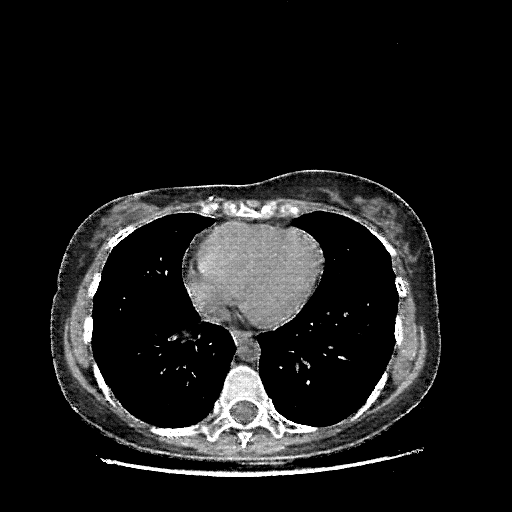

Image Grid

4Γ—3 grid: Rows show different image types (Original NATIVE, Reconstructed NATIVE, Original VENOUS, Generated VENOUS), Columns show windowing techniques (No Window, Lung Window, Mediastinum Window)

Original VENOUS CT scan

Full window (WL 1023.5, WW 4095 β†’ Low βˆ’1024, High +3071)

Lung window (WL -600, WW 1500 β†’ Low βˆ’1350, High +150)

Mediastinum window (WL 40, WW 400 β†’ Low βˆ’160, High +240)